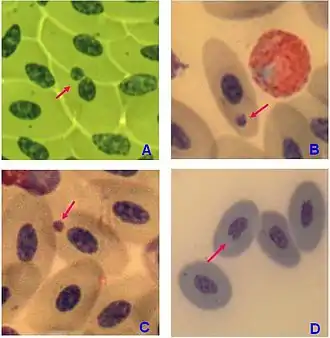

Chromatin bridge is a mitotic occurrence that forms when telomeres of sister chromatids fuse together and fail to completely segregate into their respective daughter cells. Because this event is most prevalent during anaphase, the term anaphase bridge is often used as a substitute. After the formation of individual daughter cells, the DNA bridge connecting homologous chromosomes remains fixed. As the daughter cells exit mitosis and re-enter interphase, the chromatin bridge becomes known as an interphase bridge. These phenomena are usually visualized using the laboratory techniques of staining and fluorescence microscopy.[1][2]

Chromatin bridges may form by any number of processes wherein chromosomes remain topologically entangled during mitosis. One way in which this may occur is the failure to resolve joint molecules formed during homologous recombination mediated DNA repair, a process that ensures that replicated chromosomes are intact before chromosomes are segregated during cell division. In particular, genetic studies have demonstrated that the loss of the enzymes BLM (Bloom's Syndrome Helicase) or FANCM each result in a dramatic increase in the number of chromatin bridges. This occurs because loss of these genes causes an increase in chromosome fusions, either in an end-to-end manner or through topological entrapment (e.g., catenation or unresolved DNA cross-links), have also been associated with chromatin bridge formation. When viewed under a fluorescence microscope and immunostained for cytological markers, these chromatin bridges appear to emanate from either centromeres, telomeres or DNA crosslinks (as marked by FANCD2).[4]

Detection

Chromatin bridges are easiest and most readily visible when observing chromosomes stained with DAPI. DNA bridges appear to be a blue, “string-like” connection between two separated daughter cells. This effect is created when sticky ends of chromosomes remain connected to one another, even after mitosis. A chromatin bridge may also be observed using indirect immunofluorescence, in which anti-tubulin emits a green coloration when bound to microtubules in the presence of UV light. Because microtubules maintain the positions of the chromosomes during mitosis, they appear to be densely pinched between the two dividing, daughter cells. Chromatin bridges can be difficult to locate utilizing fluorescence microscopy, as this phenomenon is not incredibly abundant and tend to appear faint against the dark background.

Recently, chromatin bridges have been implied as a diagnostic marker for cancer, while having been linked to tumorigenesis in humans.[5] This premise is based on the fact that as the mitotic cell divides and the daughter cells move further apart, stress on the DNA bridge leads to breakages in the chromosome at random points. As previously stated, the disruptions in the chromosome may lead to single chromosome mutations, including deletion, duplication and inversion, among others. This instability, defined as frequent changes in chromosomal structure and number, may be the basis of the development of cancer. While the frequency of chromatin bridges may be greater in tumor cells relative to normal cells, it may not be practical to utilize this phenomenon as a diagnostic tool. The process of staining and mounting sample cells using indirect immunofluorescence is time-consuming. Even though DAPI staining is quick, neither laboratory technique can guarantee the presence of the bridges under the fluorescence microscope. The rarity of chromatin bridges, even in cancerous cells, makes this phenomenon difficult to be widely accepted diagnostic marker for cancer.